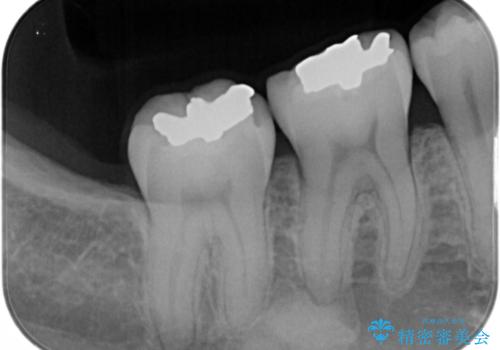

- 矯正治療が終了して歯並びが綺麗になると、元々入っていた銀歯が気になってきたとのことで適合の良いセラミックへのやり替えを行いました。

適合不良の補綴物は二次的な虫歯発生のリスクが高まります。

自費診療で用いられる材料は保険適応の材料に比べて、より精密で適合の良い被せ物作ることができるため、長期的な虫歯のリスクを大幅に減らすことが可能です。